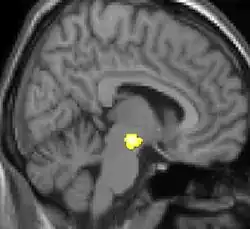

As reais causas da cefaleia em salvas (CES) ainda são desconhecidas, mas, de acordo com alguns estudos, os padrões das crises, as influências pelo horário do dia e as estações sugerem que o relógio biológico do corpo está envolvido. Nos seres humanos, o relógio biológico está situado no hipotálamo. Durante um ataque, o hipotálamo libera substâncias químicas que podem estimular as células nervosas no cérebro, causando dor e outros sintomas. A hiperatividade nervosa também pode causar um alargamento (vasodilatação) das artérias no lado afetado do cérebro. Uma teoria é que as dores são causadas por um alargamento dos vasos sanguíneos, que pressionam sobre os tecidos nervosos próximos, causando dor.[5] Exames de ressonância magnética sugerem dilatação da artéria oftálmica durante uma crise de cefaleia, enquanto a tomografia por emissão de pósitrons (PET) revela atividade dentro do seio cavernoso. Em alguns casos, existem fatores genéticos também, pois é mais comum entre familiares.[6]

As CES são ocasionalmente chamadas de "dores de cabeça despertador" por causa da regularidade de sua ocorrência e que pode despertar as pessoas do sono. Ambos os ataques, os individuais e o agrupamento "salvas" pode ter uma regularidade. É normal que os ataques se iniciem em um momento preciso do dia ou da noite. O agrupamento de CES pode ocorrer com mais frequência em torno dos solstícios, às vezes apresentando periodicidade circanual. Isso levou os investigdores a especular o envolvimento do hipotálamo (incluindo a possibilidade de uma disfunção no mesmo), que controla o "relógio biológico" do corpo e o ritmo circadiano. Por outro lado, a frequência de ataque pode ser muito imprevisível, não mostrando nenhuma periodicidade.